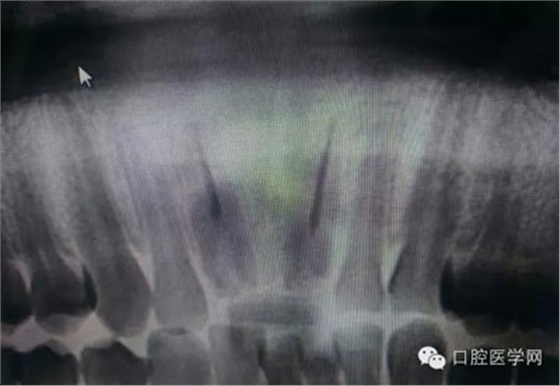

根管再治療是我們比較頭疼的,尤其是那些冠修復(fù)過(guò)的,我們有很多的麻煩需要去溝通,比如可能導(dǎo)致的側(cè)穿、可能沒有看到的腐質(zhì)、可能導(dǎo)致的崩瓷,或者是后期可能出現(xiàn)冠折......這些需要我們和患者好好的溝通。全瓷冠還好些,金屬冠根測(cè)的時(shí)候很是麻煩,總之我們做修復(fù)的時(shí)候不要單純的追求速度,追求效益,適當(dāng)?shù)淖⒁庀挛覀兊幕A(chǔ)治療和設(shè)計(jì)。